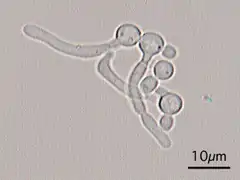

Candida Albicans Yeast forms (round-to-oval)

Candida Albicans Hyphal forms (filamentous projections called hyphaes emerging from round-to-oval forms)